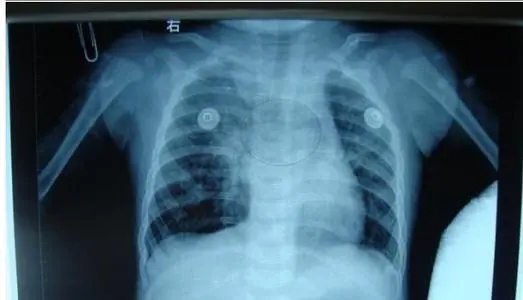

縱隔疝的診斷主要依賴胸部X線檢查,后前位胸片和縱隔肺門常規(guī)斷層片可見局部透亮區(qū)域超過氣管軸線,是肺組織疝入對側胸腔的征象,疝入對側的肺組織內很少 見肺紋理,胸部CT可以清晰地顯示縱隔疝的部位和范圍,對于確診價值很大,此外,胸部X線檢查多有助于明確導致縱隔疝的原發(fā)疾病的診斷。